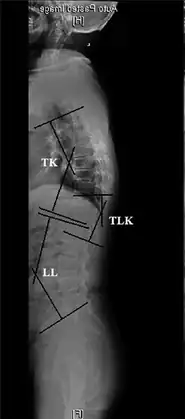

TK: Thoracic kyphosis- Measurements of spinopelvic parameters

Sagittal balance measurement.[7]

Kyphosis can be graded in severity by the Cobb angle. Also, sagittal balance can be measured. The sagittal balance is the horizontal distance between the center of C7 and the superior-posterior border of the endplate of S1 on a lateral radiograph.[7]